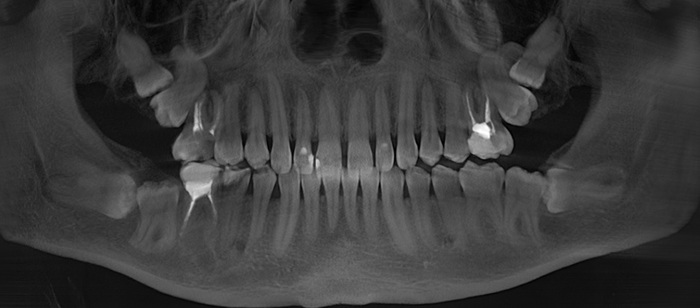

Я подготовился к приему заранее, посмотрел компьютерную томографию, которую он мне прислал.

По снимку видно, что необходим комплексных подход к проблеме, который будет включать в себя мою работу, как хирурга, так и смежных специалистов. Гигиениста, ортопеда и терапевта.

Согласитесь, не особо эстетично. Ортопантомограмма: